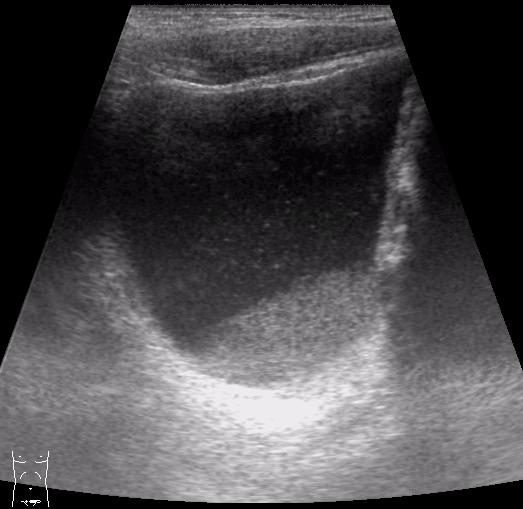

KapustinSV писал(а):Уретероцеле вижу, а признаков острого цистита - нет.

точно! уретероцеле тут первично, а цистит вторичный!

(вот по-этому и нет специфических узи-признаков!) :oops: